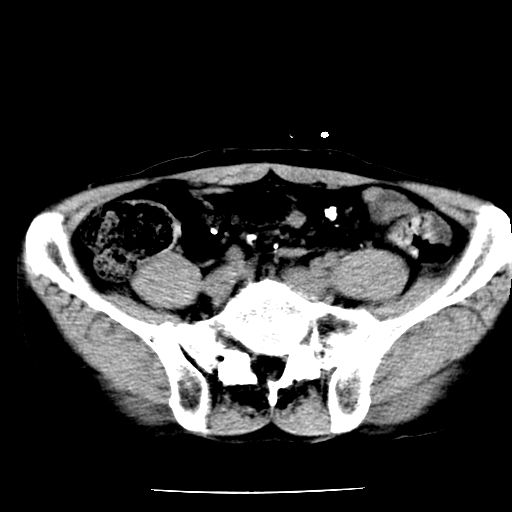

男,59岁,“结核性胸膜炎”30余年,胸部经常疼痛,多次x检查提示“肺部”炎症。腹部疼痛5日,b超提示:“肝内短管结石,余显示不清,建议进一步检查。”

两肺结核并右侧胸腔积液;脾脏、腹腔及腹膜后淋巴结结核[陈旧性];肝内胆管结石

胸部腹部都是结核(双肺。纵隔淋巴结,肝脏,脾脏,肠系膜)

两肺结核并右侧胸腔积液;脾脏、腹腔及腹膜后淋巴结结核[陈旧性];肝内胆管结石。直肠息肉?